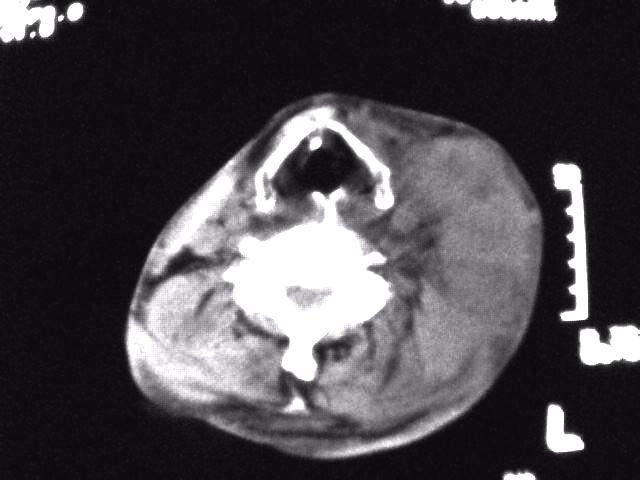

颈部层厚10mm间距10mm连续扫描及增强扫描共24层示:左侧下颈部胸锁乳突肌内侧区域内可见多发软组织结节,密度不均,内可见斑片状低密度区,大小不等,部分融合成块,左侧融合成一块者大约9.0x5.4,与周围肌肉、血管等结构界面不清,骨质未见明显浸润影。左侧锁骨下可见多个软组织结节,与周围界限尚清,左侧锁骨上窝内可见一大软组织肿物,大小约4.7x3.7cm,内密度欠均匀中心可见低密度区。

考虑:左侧颈部及双侧锁骨下多发淋巴结肿。非何杰金氏淋巴瘤可能性大,建议进一步检查。